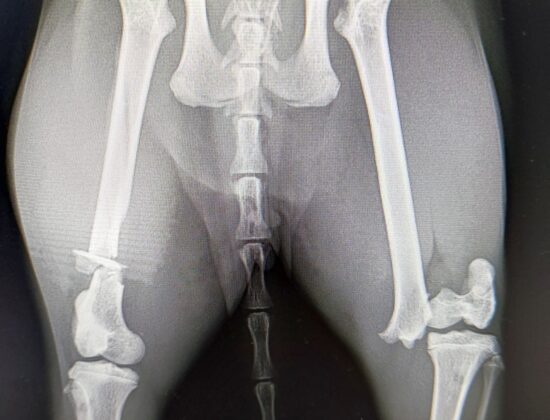

Gestern haben wir diese angefahrene Fundkatze aus Pützborn gemeldet bekommen.

Wie man sehr deutlich sehen kann, sind beide Hinterläufe gebrochen.

Wir haben sie über Nacht aufgenommen und mit reichlich Schmerzmittel versorgt.

Zum Glück hat sich der Besitzer gemeldet, deshalb haben wir die Katze heute Vormittag nach Absprache noch in eine Tierarztpraxis gefahren und damit ist unser Auftrag erledigt. Der nächste Notfall ist schon angemeldet und braucht die Quarantänebox.